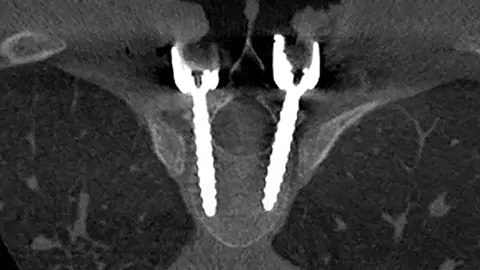

Verbesserte Darstellung der Wirbelsäulenanatomie für präzise Planung und effektive Implantatplatzierung

Mit der Anzahl der minimal-invasiven Wirbelsäuleneingriffe steigt auch der Einsatz von Hybrid-Operationssälen (Hybrid-OPs). Das Team für Orthopädie und Unfallchirurgie am Universitätsklinikum Schleswig-Holstein (UKSH) berichtet über die Vorteile, die ihnen der Philips Hybrid-OP in den letzten drei Jahren bei minimal-invasiven Wirbelsäuleneingriffen gebracht hat.